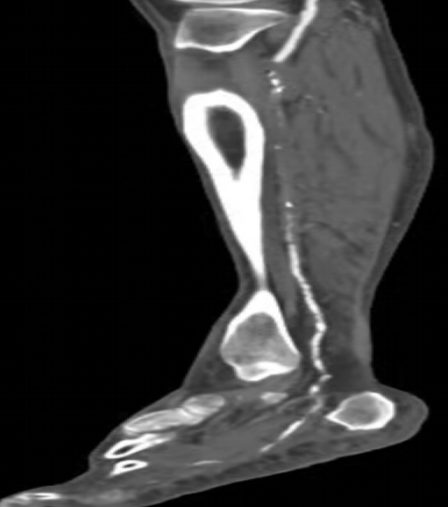

情急之下去了當地醫(yī)院,醫(yī)生一瞧告訴王大伯:“您這可能是糖尿病足,你這傷口肯定是長不好了,需要外科手術清創(chuàng)、植皮,如果還是長不好就要截肢”。聽了醫(yī)生的話,王大伯出了一身冷汗,幾經周折最終來到了我院血液內分泌科,住院后進行下肢動脈超聲及CTA發(fā)現:雙下肢膝下動脈節(jié)段性狹窄、閉塞。診斷為:右下肢動脈硬化閉塞癥(Runtherford6級),糖尿病下肢嚴重缺血(右側),右足潰瘍;經多學科會診初期"改善循環(huán)、控制血糖、抗感染、局部清創(chuàng)換藥、營養(yǎng)神經、支持治療"六環(huán)法措施下,老伯潰瘍雖有好轉,但仍不能完全愈合,右足仍靜息下疼痛。

下肢動脈CTA